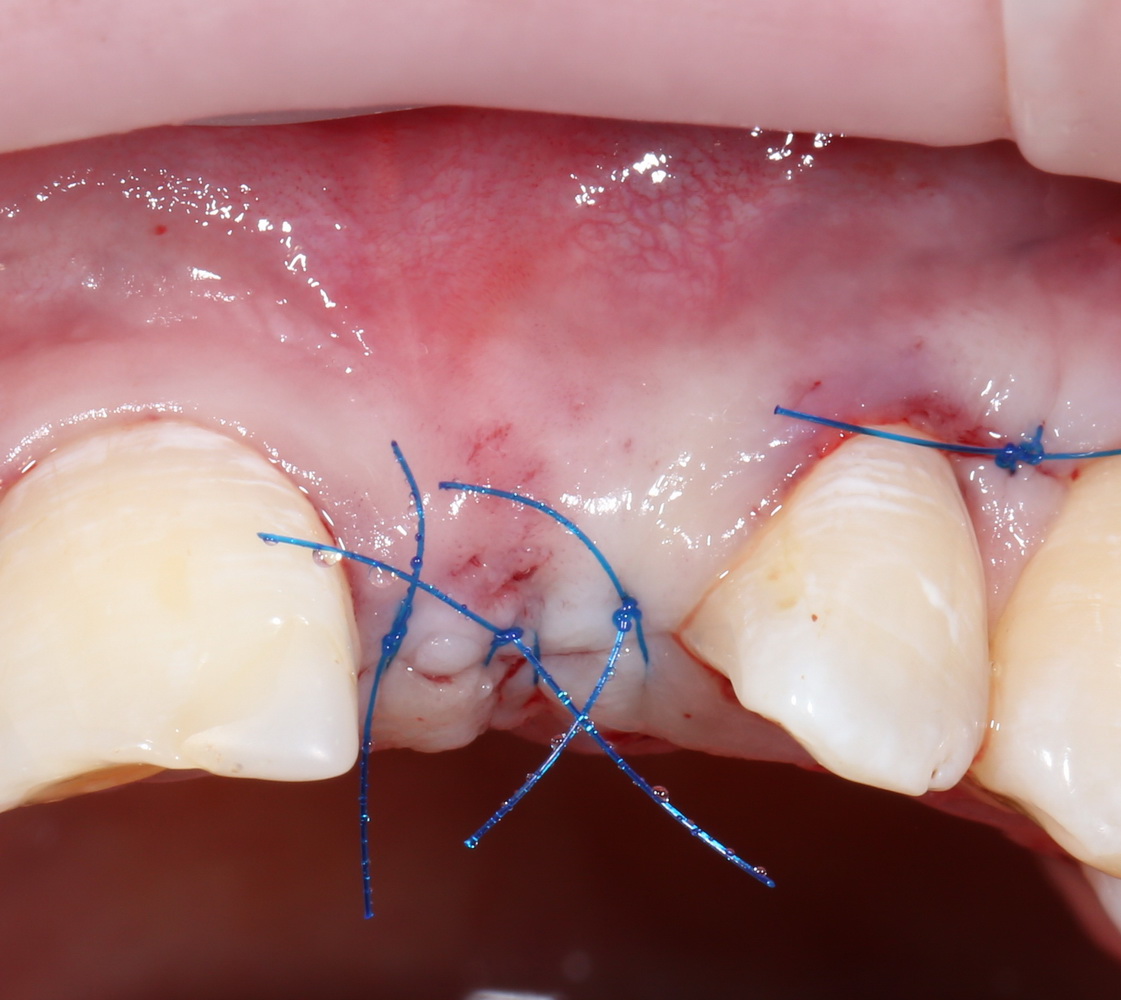

Ну и, швы:

Друзья, он очень простой. Это швы. От качества швов зависит очень и очень многое.

Если при работе с костными блоками в случае расхождения швов у нас есть шанс сохранить результат, то при попадании инфекции из полости рта в область трансплантата, состоящего из аутокостной стружки, он сам быстро превращается в рассадник инфекции — ни промыванием, ни повторными швами удержать объем и результат не удается. С этой точки зрения, описываемая методика гораздо более деликатная и ранимая. Инфекцией, разумеется.

Но, в принципе, если на протяжение послеоперационного периода удается сохранить рану герметичной — результат будет. Обязательно.

Поэтому забываем викрил и другие плетеные материалы. Только нерезорбируемая мононить (Prolene, Resoprene и т. д.), только хардкор.